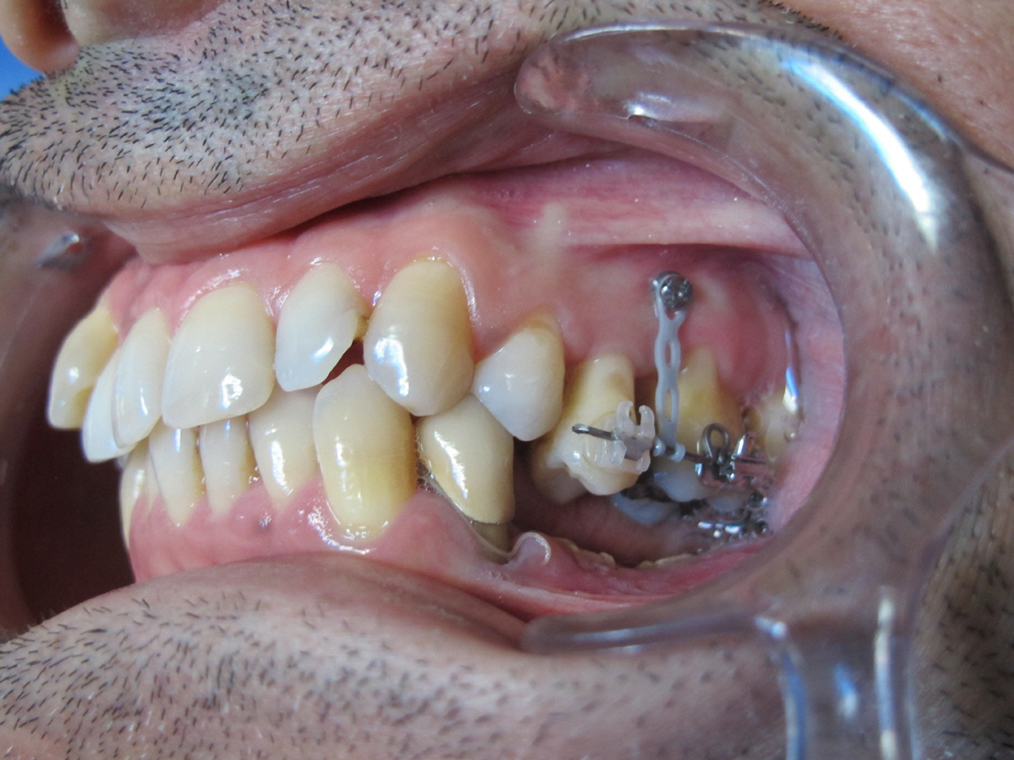

Arcade maxillaire avant traitement orthodontique, séquelles de maladie parodontale